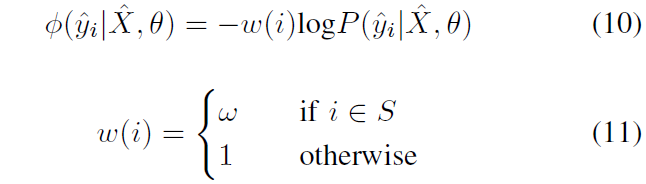

ϕ

- P ( y ^ i ∣ X ^ , θ ) P(\hat y_i | \hat X, \theta) P(y^i∣X^,θ):是 CNN 的 softmax layer 的输出概率

当 P P P 越大, ϕ \phi ϕ 就越小,这样就达到了最小化能量函数的目的。

3. Weighted Loss Function during Network Update Step

在 CNN 网络的更新阶段,会根据当前的分割结果 Y ^ \hat Y Y^ 进行 fine-tuning。作者提出的 fine-tuning 不是对所有像素都进行处理,而是根据各像素的 confidence 对它们进行处理(对比之前有的方法是对所有像素都进行处理)。

比如说,用户提供的 scribbles 相比其他像素要具有更高的 confidence,所以就对 loss function 有更大的影响,因此对公式(3)即一元项进行加权:

权重为

w

(

i

)

w(i)

w(i),其函数定义表示了若像素

i

i

i 属于用户提供的 Scribble,则其权重为

w

w

w,否则权重为 1。

对公式(9)进行加权得到:

--------最终我们需要优化的目标函数就是 (10) , (12)---------